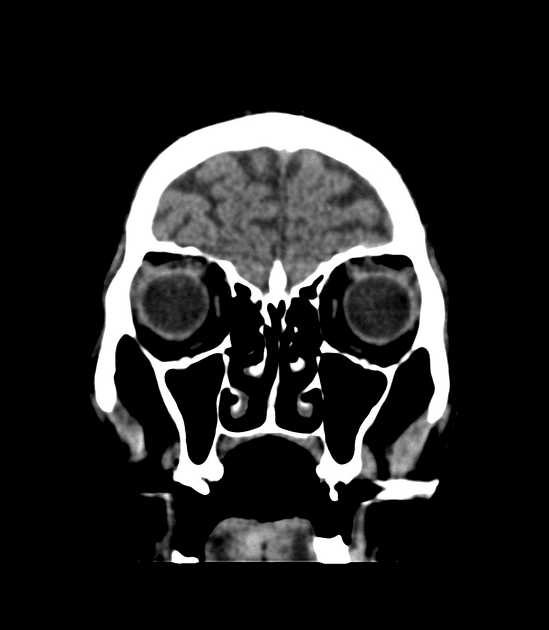

- Hoại tử xuất huyết (hemorrhagic necrosis) nhân bèo (putaminal) hai bên biểu hiện rõ qua tình trạng tăng tín hiệu (high signal) trên các chuỗi xung T1WI, T2WI và FLAIR.

- Ghi nhận có tín hiệu sụt giảm (drop out signal) trên chuỗi xung T2* GRE và hạn chế khuếch tán (diffusion restriction).

THẢO LUẬN (DISCUSSION): Việc pha trộn rượu giả là nguyên nhân phổ biến gây ngộ độc methanol (methanol intoxication) cấp tính (acute) ở các nước đang phát triển. Nhân bèo (putamina) là những vị trí dễ bị tổn thương nhất trong ngộ độc methanol; các dấu hiệu đặc trưng khác cần lưu ý bao gồm giảm tỷ trọng lan tỏa (diffuse hypo-attenuation) ở chất trắng đại não (cerebral white matter) và xuất huyết (hemorrhages).

- "Hoại tử nhân bèo hai bên là dấu hiệu hình ảnh kinh điển của ngộ độc methanol."

- "Chuyển dạng xuất huyết của các vùng hoại tử là phổ biến và được thấy dưới dạng sụt giảm tín hiệu trên T2* hoặc SWI."

- "Hạn chế khuếch tán ở nhân bèo xảy ra trong giai đoạn cấp tính do phù độc tế bào."

Ngộ độc methanol là một cấp cứu y khoa thường do uống phải rượu giả hoặc dung môi công nghiệp. Độc tính được trung gian bởi axit formic, một chất chuyển hóa của methanol, gây ức chế cytochrome c oxidase của ty thể, dẫn đến thiếu oxy tế bào. Nhân bèo đặc biệt nhạy cảm với sự tấn công chuyển hóa này, dẫn đến hoại tử hai bên và có thể kèm xuất huyết. Ngoài các hạch nền, độc tính methanol cũng có thể ảnh hưởng đến chất trắng dưới vỏ và dây thần kinh thị giác, trong đó tổn thương dây thần kinh thị giác thường dẫn đến suy giảm thị lực vĩnh viễn hoặc mù lòa.